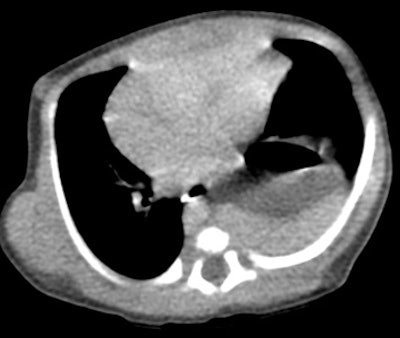

Unsuspected congenital diaphragmatic hernia: The newborn shown below presented with respiratory difficulty, but did not have a scaphoid abdomen. The frontal CXR demonstrated and abnormal lucency and curvilinear density in the left base. A lateral view revealed findings concerning for a diaphragmatic hernia. This was confirmed on CT imaging- note that a portion of the stomach and the spleen have herniated through the defect. |